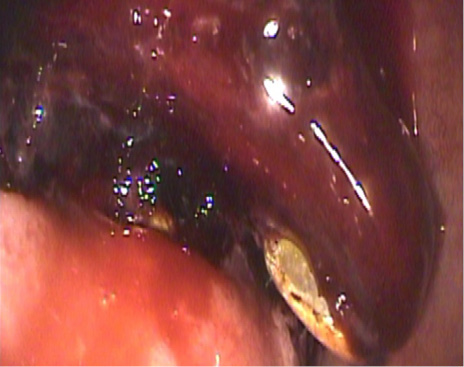

Se realiza un ultrasonido (US) que reporta vesícula biliar con pared ecogénica y esclerótica de 5 mm, litos en el interior con sombra acústica posterior y Murphy sonográfico positivo. Se realiza una endoscopia alta que reporta una úlcera duodenal gigante con coágulo adherido (Forrest IIb) (Figura 1). Se transfunden hemoderivados, se da terapia con inhibidores de bomba de protones en infusión por 72 horas y se propone la revaloración endoscópica.